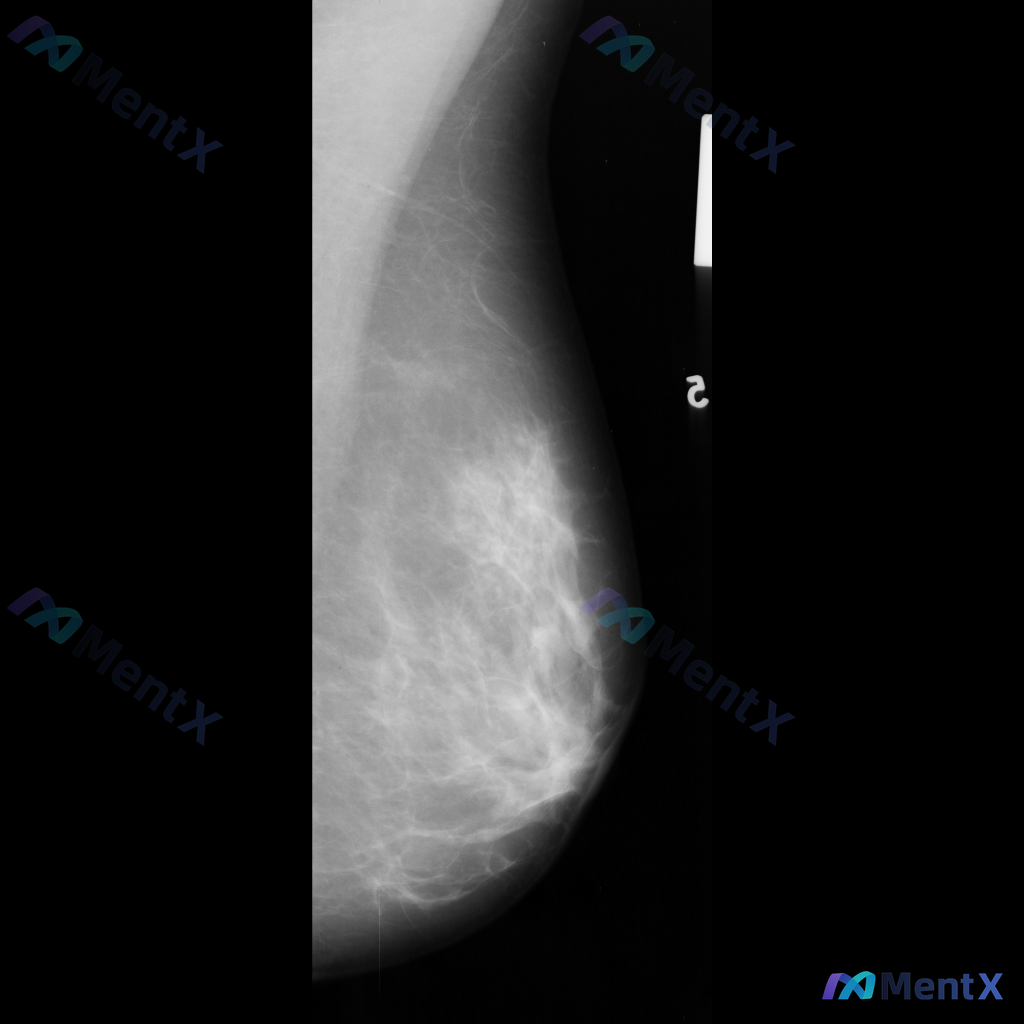

整理到一张乳腺钼靶影像资料,目前只有单张图像,没有提供双侧对比和多体位视图。 从这张图像来看,主要表现是腺体组织与脂肪组织混合存在,腺体分布相对广泛。目前没有看到非常明确的肿块、成簇钙化或明显的结构扭曲这类表现。 想跟大家讨论一下,单看目前这张影像,大家会优先考虑哪一种情况?另外,对于这类单张图像的...

整理到一张乳腺钼靶局部影像的资料,先和大家同步一下读片描述: 影像主要显示乳腺呈多量腺体型,纤维腺体组织丰富,密度较高;目前未见明确的局限性肿块、钙化、结构扭曲或不对称致密影这类病理性异常征象。 不过提供的只是单张局部影像,没有对侧乳腺对比,也没有完整的CC/MLO位,更没有临床病史(比如年龄、有没...

整理到一张单侧乳腺钼靶影像的读片资料,目前是单一体位图像,没有双侧对比。 影像表现整理 - 乳腺组织密度较高,属于多量腺体型或致密型背景 - 可见散在的钙化灶:图像中部偏下有数个点状或粗大钙化,形态不规则,但无典型恶性钙化的细小多形性、线样或分支状表现 - 乳腺下象限可见多个高密度圆形/卵圆形影,边...

整理了一份乳腺影像的读片资料,想和大家讨论下判断方向: 基本影像信息 - 单侧乳腺X光片,投照体位考虑可能为内外斜位(MLO) - 乳腺组织构成:不均匀致密型 - 影像质量:曝光适中,清晰度良好,无明显伪影 - 可见结构:皮肤、皮下脂肪层、乳头乳晕、Cooper韧带显示尚可;未见明确钙化血管或腋窝淋...